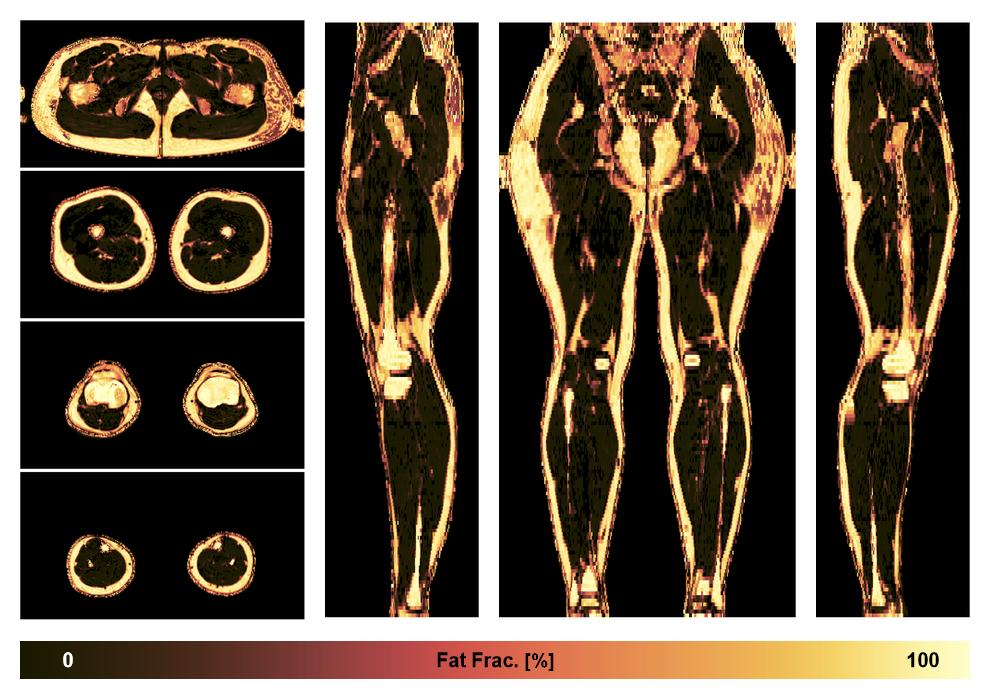

• Fat fraction

The fat fraction of the lower extremity obtained from the dixon reconstruction for muscle water fat quantification.